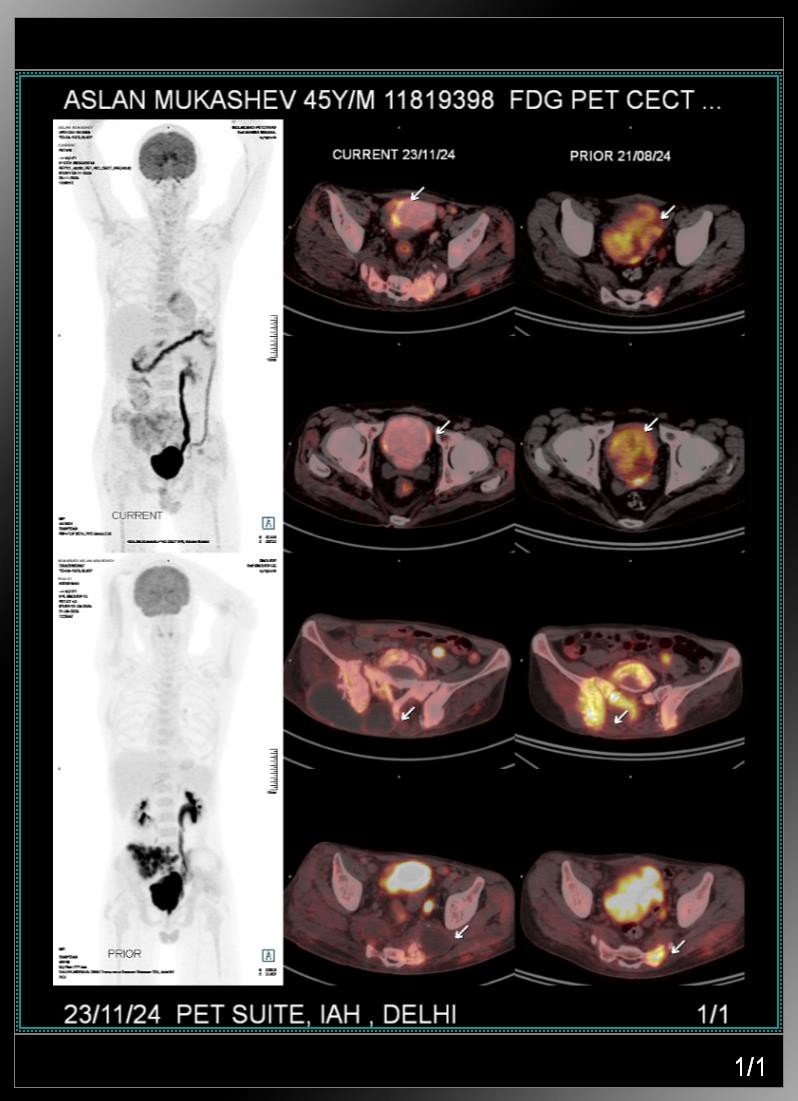

PET CT (21.08.2024) (Translated)

- Recurrence of the main cancer disease FDG avid urinary bladder wall thickening.

- Signs of secondary (mets) damage to skeletal bones (L4, L5 vertebra, sacrum, iliac bones bilateral with high metabolic

activity).

- Mild uptake in the line of the inguinal groups bilateral are suspicious of secondary (mets).

- Left side hydroureter nephritis.

- Concretions in urinary bladder.

PET CT reviewed in India

PET CT CD review revealed extensive mets in right sacrum, ileum and other skeletal mets.